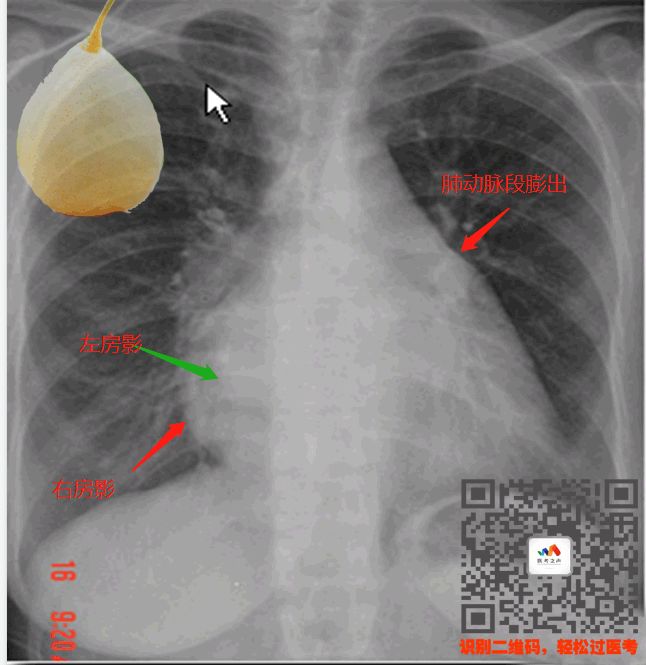

① 二尖瓣型心(梨型心)

特点:心脏像个梨子

二尖瓣型心

就是二尖瓣出了问题导致心脏变形

二尖瓣狭窄以后,左心房的血流不出

造成左心房增大,跟右心房重叠(双房影)

肺动脉的血液也没地方流(肺动脉段增粗)

这时候就会造成心腰饱满

就像一个梨子一样

看图